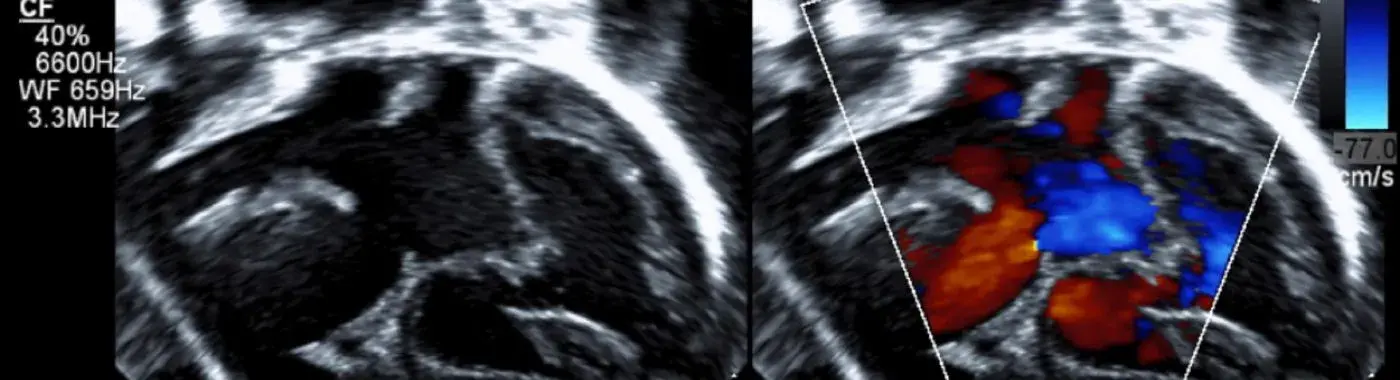

• Echocardiogram: This ultrasound test provides images of the heart's structure and function, allowing for the visualization of the aortic valve.